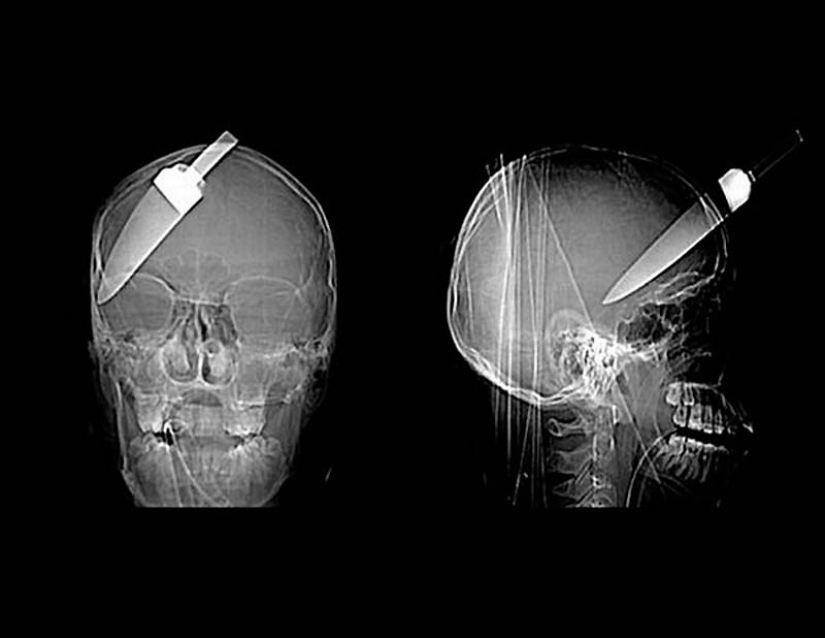

9. The severed finger of a patient who fought with a man armed with a knife.

11. A spear from a harpoon that hit a 16-year-old boy in the head on a fishing trip.

15. A knife in the head of a 10-year-old boy. The boy survived.

18. a 12-centimeter knife in the skull of a teenager.